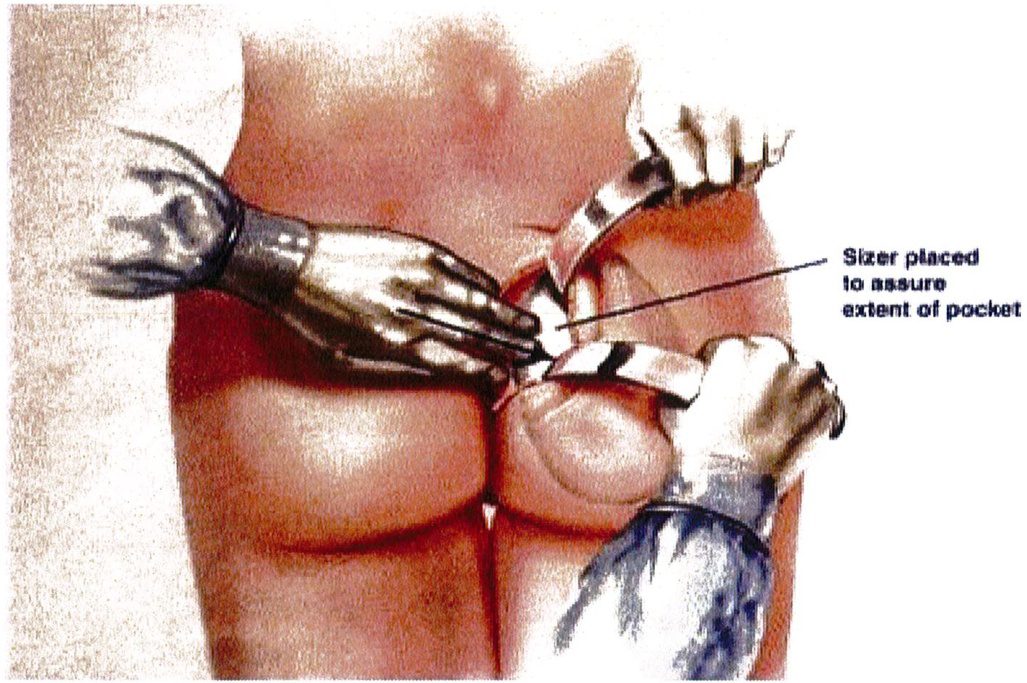

rằng cả hai bên túi được bóc tách trước khi đặt mô cấy để dễ dàng căn chỉnh hai bên cho cân đối (Hình 12 và 13). Sau khi bóc tách xong, sử dụng các sizer đặt vào mặt phẳng vừa bóc tách để xác nhận lại kích thước khối implant phù hợp cho bệnh nhân (Hình 14).

Hình. 14. Sau khi hoàn thành việc đặt túi, hãy đặt 1 sizer vào để đánh giá tính cân đối và thể tích khoảng không gian bên trong đó. Chú ý khối implant phải vừa khít với túi. (From de ia Pena jA, Kubio ÜV, Cuno JP, et al. Subfascial Näng mong. Clin Plast Surg 2006; 33:414; đã xin phép trước khi đăng tải.)